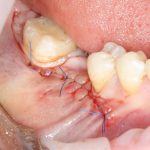

9. Наложение швов.

Я ни разу не испытывал каких-то проблем с ушиванием операционной раны. Как правило, её края сходятся достаточно легко без дополнительной периостотомии. Для наложения швов мы используем монофиламентные нерезорбируемые нити диаметром 5-0 (Resolone, Prolene, Полипропилен и др.).